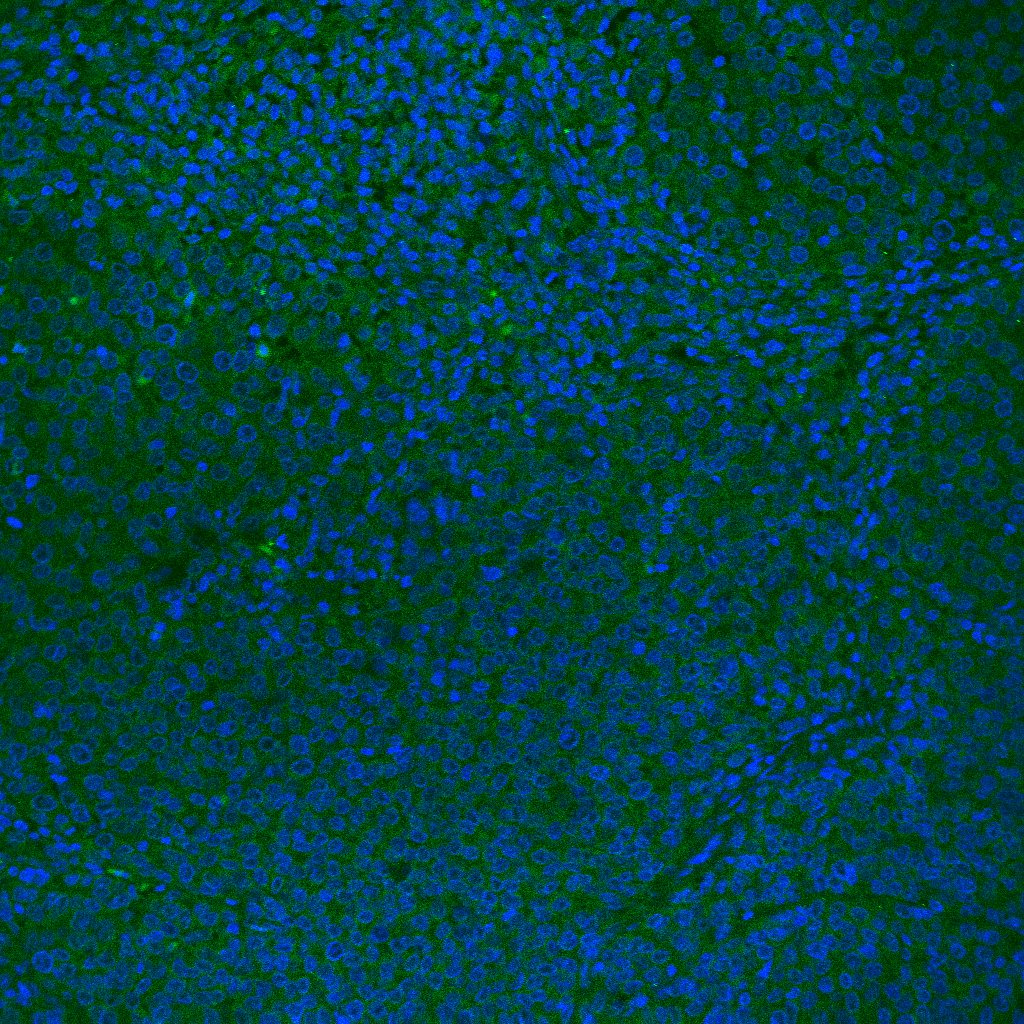

Detection of G-CSF by Immunohistochemistry G-CSF, but neither IL-17 nor Bv8, was still essential to the intratumor recruitment of PMN-MDSCs and antitumor angiogenesis in the LLC tumor model(A) Confirmation that G-CSF, but not IL-17, was involved in anti-VEGF-mediated upregulation in LLC tumor lysate assessed by ELISA assay. (n = 6/group). (B) Neither anti-VEGF nor capecitabine affected Bv8 expression as assessed by ELISA. (n = 6/group). (C) Effects of anti-VEGF, anti-G-CSF, and their combination on LLC tumor angiogenesis. The PECAM-1-positive vascular surface area was identified by immunohistochemistry. Only the combination, but not either sole therapy, could reduce the tumor angiogenesis. (n = 6/group). (D) Effects of anti-VEGF, capecitabine, and their combination on LLC tumor angiogenesis. The PECAM-1-positive vascular surface area was identified by immunohistochemistry. Note that only the combination, but not either sole therapy, could reduce the tumor angiogenesis, similarly to the findings to shown in panel (C). Data are mean ± SEM. N.S.: not significant, *P < 0.01, and #P < 0.05. (n = 5–6/group). Image collected and cropped by CiteAb from the following open publication (https://pubmed.ncbi.nlm.nih.gov/29707135), licensed under a CC-BY license. Not internally tested by R&D Systems.